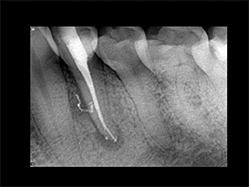

Slika 3: Nekrotičan/zaražen zub: donji premolar pacijenta koji se žali na konstantan, pulsirajući bol. Infekcija nije ograničena samo na apikalni deo već je takođe locirana i u srednjem delu lateralnog kanala. Postoperativni rendgenski snimak pokazuje 3-D zaptivanje apikalne regije sa svim anastomozama lateralnog i pomoćnih kanala.